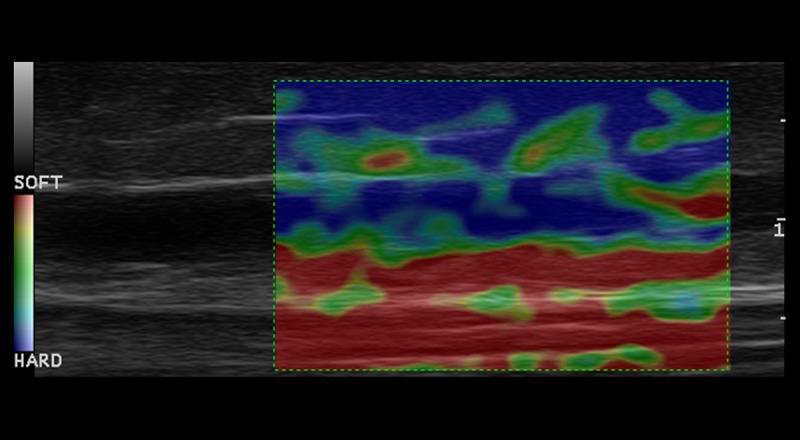

On the sixth day after the treatment 31 patients presented uniform, hypoechogenic thrombus in B-mode image. Ultrasound-based elasticity images (elastography) showed significant predominant red and green areas. Blue area was either invisible or appeared in insignificant grade on examined area. The mosaic image of colors appeared on 2 patients. On the fourteenth day of study 21 patients still presented hypoechogenic thrombus, whereas mixed echogenicity of thrombus appeared on 11 patients. On 28 examined patients mosaics of red, green and blue colors were observed, with blue color significantly predominating over red color. 3 patients presented mosaics of colors without a predominate color.

治疗后第六天,31例患者在B超图像中呈现均匀的低回声血栓。基于超声的弹性图像(弹性成像)显示显著的主要红色和绿色区域。蓝色区域要么不可见,要么在检查区域以不显著的等级出现。2例患者出现彩色镶嵌图像。在研究的第十四天,21例患者仍呈现低回声血栓,而11例患者的血栓出现混合回声。在28例检查患者中观察到红色、绿色和蓝色的彩色镶嵌,其中蓝色显著多于红色。3例患者出现无主导颜色的彩色镶嵌。